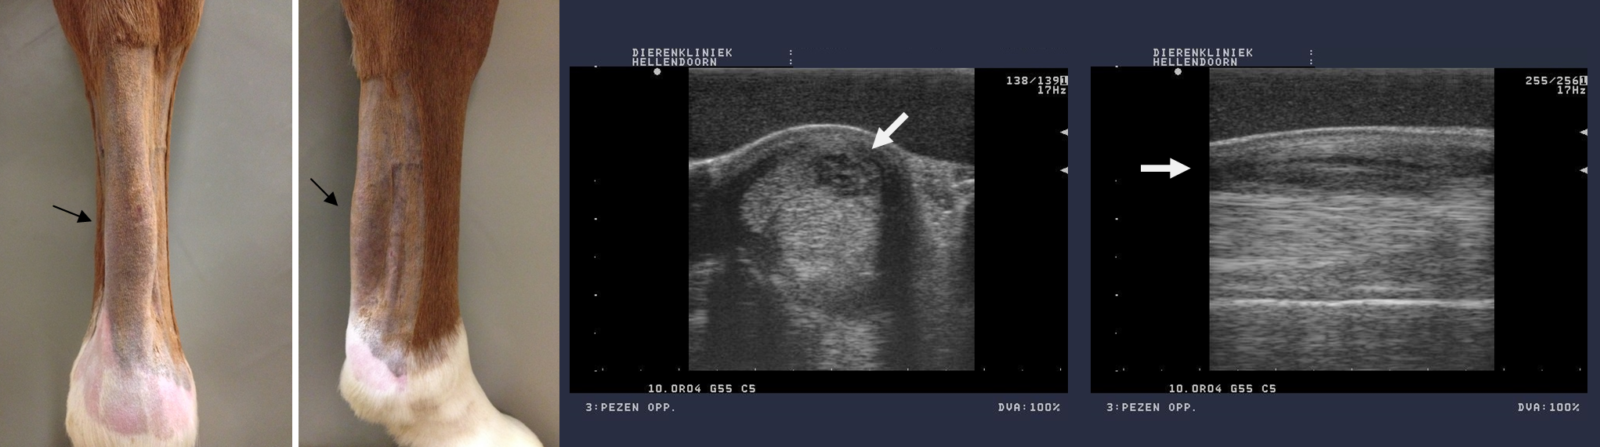

Oppervlakkige buigpees (verschil tussen linker en rechter been is goed te zien):

Echobeelden ernstige diepe buigpees laesie achterbeen: